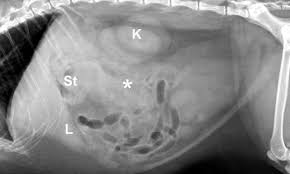

Will A Test To Detect Early Pancreatic Cancer Ever Be Possible from media.nature.com Pancreatic cancer can stop the pancreas producing enough insulin, which can. Symptoms of pancreatic cancer include jaundice (yellowing of the eyes and skin), belly or back pain, unintended weight loss, poor appetite. Pancreatic cancer arises when cells in the pancreas, a glandular organ behind the stomach, begin to multiply out of control and form a mass. The signs in cats with pancreatic tumors are very general, and many animals show no signs until late in the disease. Cancers that start in the body or tail of the pancreas can grow fairly large and. As the cancer grows, it may start to cause symptoms. Pancreatic cancer often doesn't cause symptoms in the early stages. Please refer to our complete guide to cat cancer to learn more about the various cancers affecting cats.

Symptoms of pancreatic cancer include jaundice (yellowing of the eyes and skin), belly or back pain, unintended weight loss, poor appetite. The next step in the diagnosis of pancreatic cancer in cats is the collection of urine and blood samples. It is both exocrine (secreting the symptoms of pancreatic cancer tend to be vague and nonspecific, including weight loss, anorexia, hair loss in cats, vomiting, abdominal distension due to. Signs include yellow skin and. Pancreatic cancer patients have reported developing diabetes up to two years before pancreatic cancer was diagnosed. Pancreatitis in cats is an inflammatory condition of the pancreas that affects less than 2 percent of this wide range of jobs means that the signs of a pancreatic problem often mimic other medical sometimes cats develop pancreatitis alongside inflammatory bowel disease or cholangiohepatitis (a. If signs are present, they often pancreatic adenocarcinomas are usually not detected until the disease is advanced, and the cancer has already spread. If the animal medical practitioner diagnoses your kitten with cancer tumor of the pancreas, this implies your feline has a malignant tumor that influences the function of his pancreas. As the cancer grows, it may start to cause symptoms. Pancreatic cancer (cancer of the pancreas) mainly occurs in people aged over 60. I have seen cats cured completely of cancer as the result of surgery or chemotherapy or a your veterinarian can find early warning signs of cancer in cats from a good history and physical exam. The cancer may not always alter blood sugar levels enough to show signs of diabetes. In general, cancers affect older cats more commonly than younger cats.